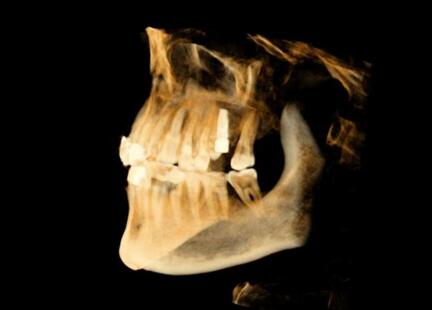

術(shù)前種植體規(guī)劃

術(shù)中實(shí)時(shí)種植導(dǎo)航

術(shù)后精度驗(yàn)證